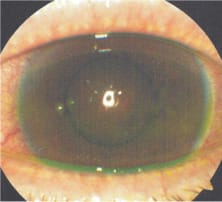

Figure 2 was taken one week later after the patient had worn redesigned LDS lenses for about three hours. Blanching of the conjunctival vessels and chemosis are prominent.

Figure 2. A redesigned large-diameter scleral lens resulted in blanching of conjunctival vessels and chemosis.